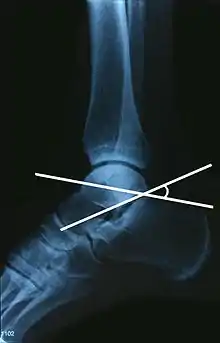

L'angle de Gissane, ou angle critique, est l'angle formé par les parties descendante et montante de la face supérieure du calcanéus. Sur une radiographie de profil, un angle de Gissane supérieur à 130° suggère une fracture de la surface postérieure du ligament talo-calcanéen. L'angle de Böhler, quant à lui, est l'angle ouvert vers l'arrière et constitué par le croisement d'une ligne qui longe la face supérieure de la grande tubérosité du calcanéus et d'une autre ligne qui joint le point le plus haut du calcanéus et le point le plus haut de la grande apophyse du calcanéus. Un angle inférieur à 20° suggère un enfoncement de la facette postérieure et une possible fracture de l'os.